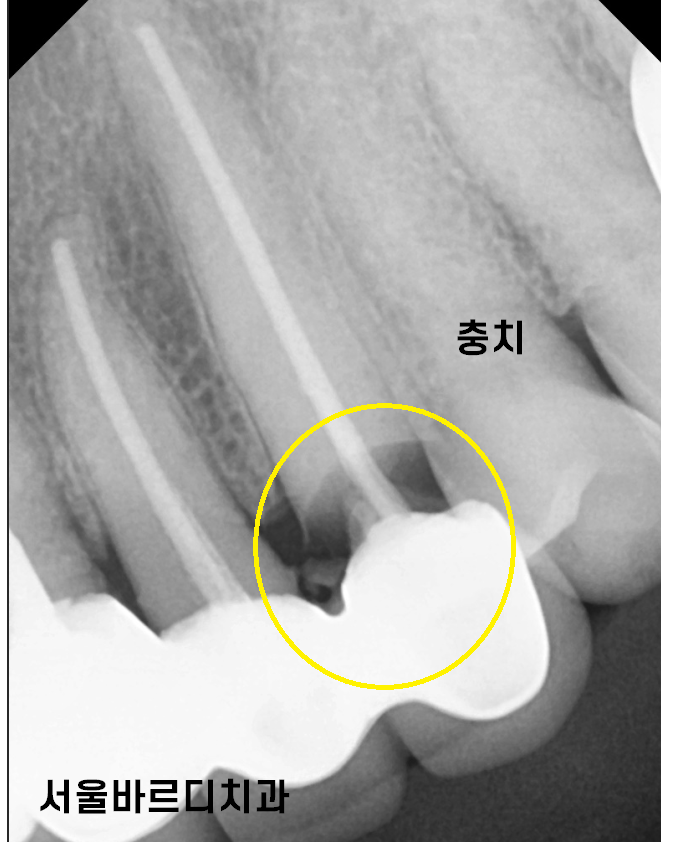

240306

왼쪽 송곳니 치아 치근 우식이 관찰됩니다.

뿌리쪽 부분이 많이 썩어

치아가 끊겨진것처럼 보이실겁니다.